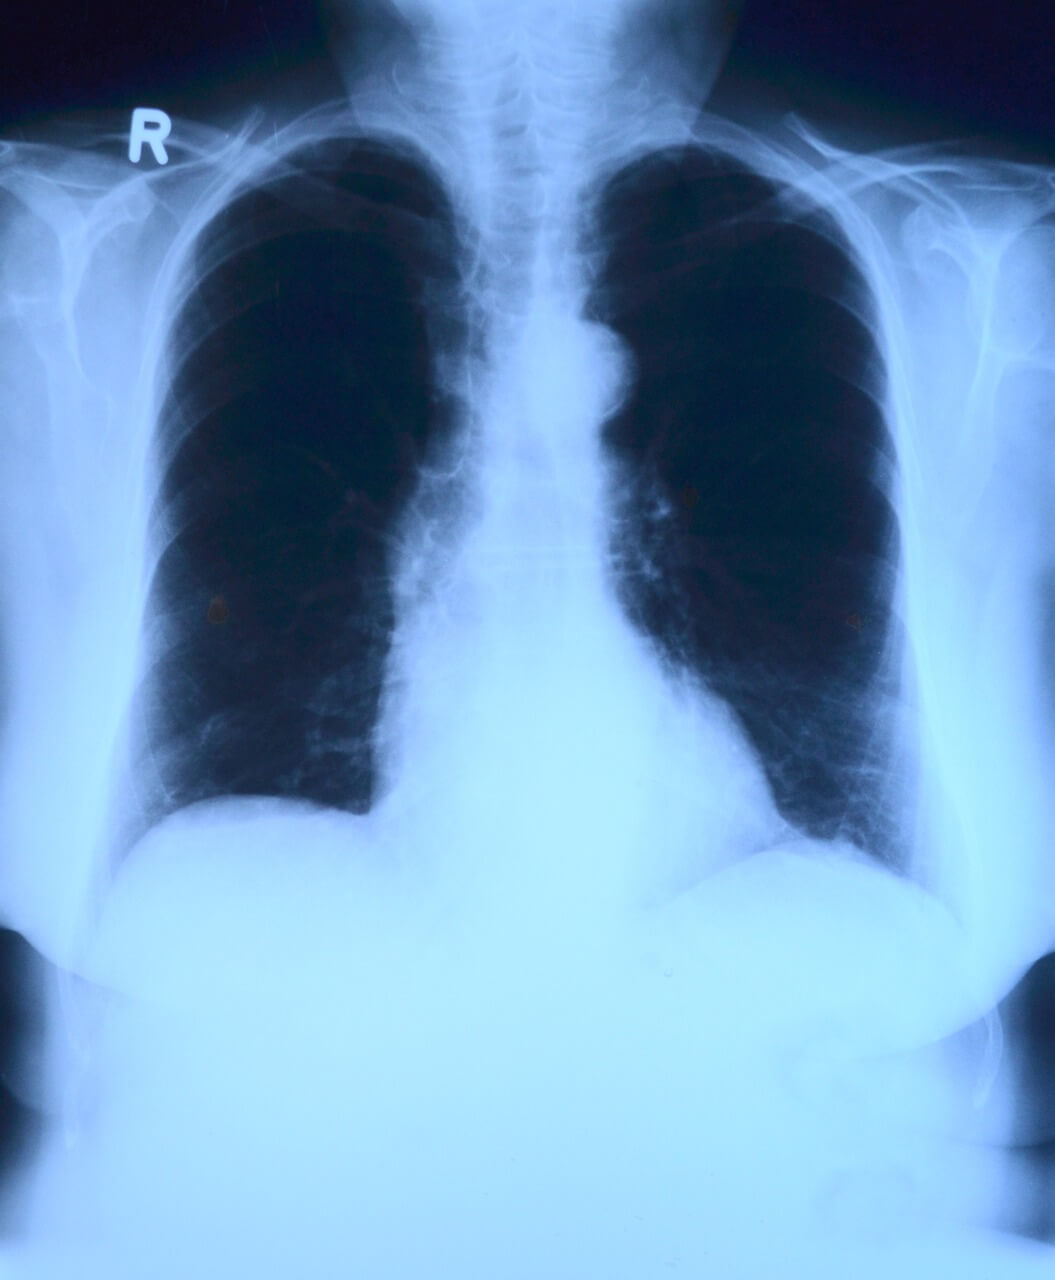

- 흉부 X-ray에서 확인 가능: 흉부 X-ray 사진에서 과거 결핵 병변의 흔적을 확인할 수 있습니다.

- 흉부 X-ray: 폐에 결핵 병변의 흔적이 있는지 확인합니다.

정기적인 추적 관찰: 흉부 X-ray 검사 및 혈액 검사를 통해 면역력 상태와 병변의 변화를 확인합니다.

| 흉부 X-ray | 과거 결핵 병변의 흔적 | 활동적인 병변 |